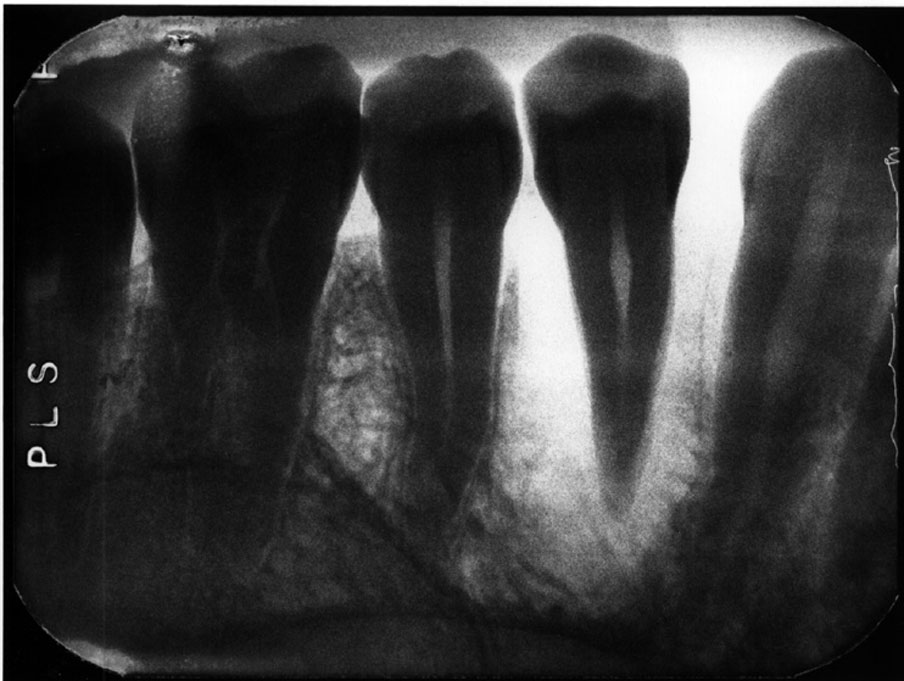

Elongation

Description: A radiograph is a two-dimensional representation of a three-dimensional object. Incorrect positioning of the tubehead’s central ray relative to the object to be radiographed results in a distorted image. If the central ray of the tubehead is placed at too shallow a vertical angle relative to the long axis of the teeth, and thus is not perpendicular to the long axis for paralleling technique or the bisector (90º angle) in the bisecting angle technique, the crown and root images will appear long (Figure 3).

Differential Diagnosis: If vertical beam angulation is too shallow, the entire tooth and roots will appear elongated. If film bending was at fault, the roots will generally be elongated, but the crown will appear normal.

Consequences: The image may still be acceptable, despite the error. If the elongation interferes with the film’s diagnostic quality, a retake is necessary.

Remedy: The operator should review technical procedures regarding vertical angulation in relation to either Paralleling or Bisecting technique, and repeat the film. The operator should increase the vertical angulation in order to correct elongation of an image.

Figure 3. Elongation.

Figure 3